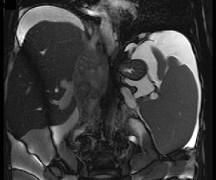

问题 女性,26岁,腹胀不适7月,腹软,肝右肋缘下1cm,影像检查如图,可能的诊断为 ( )

选项 A.肝血管瘤 B.原发性肝癌 C.肝硬化腹水 D.巴-希综合征 E.脂肪肝

答案 D